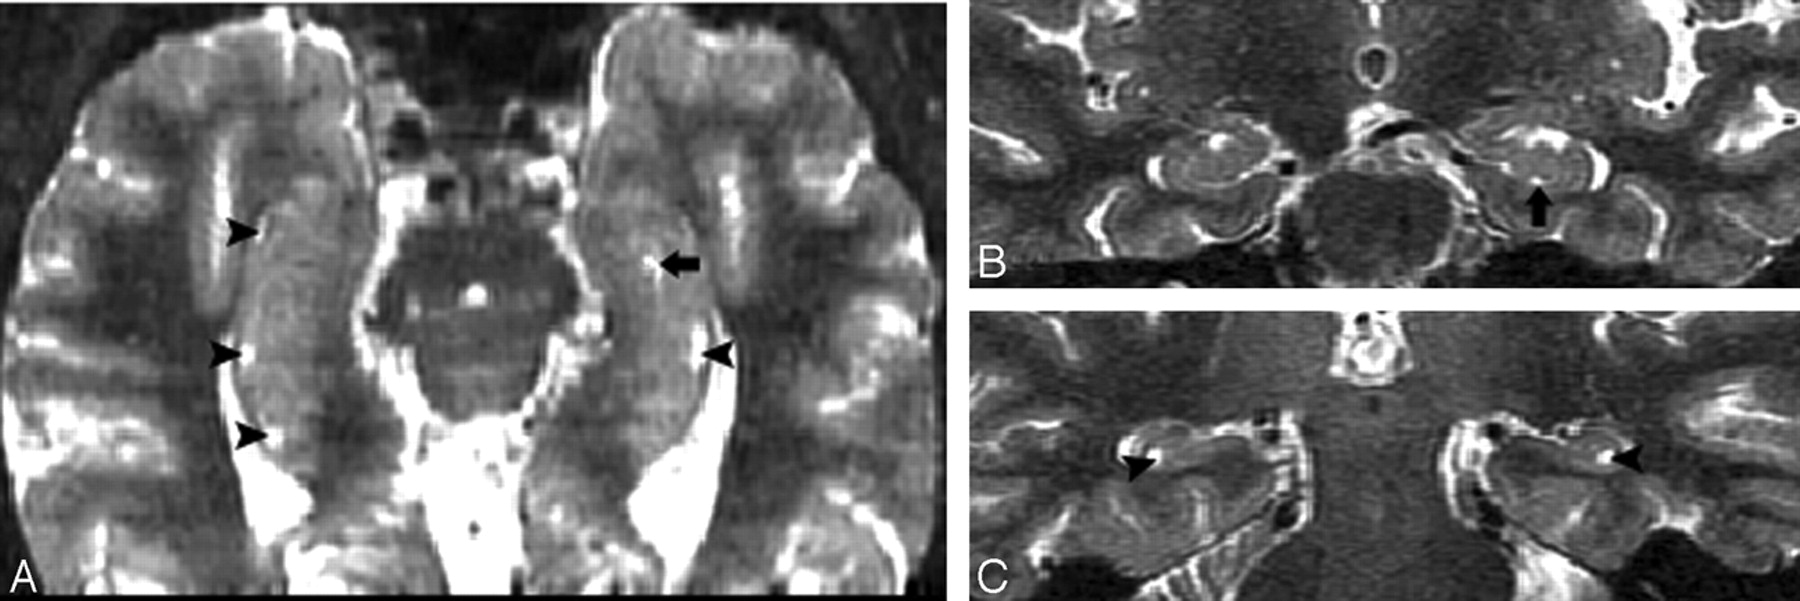

According to Duvernoy,5 at the embryonic stage, the cornu ammonis and dentate gyrus are continuous. The growing cornu ammonis increasingly bulges into the ventricular cavity (Fig 11). The primitive cornu ammonis and dentate gyrus are inverted and rolled up, so a deep cleft, the primitive hippocampal sulcus, is formed between them. This is followed by fusion of the cornu ammonis and dentate gyrus, fusion of the subiculum and dentate gyrus, and closure of the largest portion of the sulcus. This results in a residual shallow groove, the hippocampal fissure. The remnant of the primitive hippocampal sulcus is the HSC (Fig. 12).5,6 The enlargement PHF is highly correlated with hippocampal atrophy.7-11 These dilated sulci may look like cavities on some cross-section of MR imaging. These CSF spaces in hippocampus need to be distinguished, because they often form part of the clinical radiologic impression of hippocampal atrophy. Errors are common, because the anatomy can be readily misidentified.12 The key to differentiating HSC from the uncal sulcus and PHF is location. Our data show that HSC are more lateral to both PHF and the uncal sulcus and distributed along the vestigial primary hippocampal sulcus close to the ventricular margins. Another important anatomical factor is the CSF channels.

Images derived from the human hippocampus (Duvernoy, 1988)5.

A, Six-week-old embryo. Open arrow shows the primitive hippocampal sulcus.

B, Adult. Black arrow shows the hippocampal fissure; arrowhead shows residual cavity.

C, T2 coronal MR image was obtained from a 67-year-old female normal control (NC) patient. Arrowhead shows the same shape hippocampal sulcus residual cavity (HSC) as in B.

T2 MR imaging (A) and the corresponding postmortem gross specimen (B) from an 86-year-old woman with Alzheimer disease (AD), showing a crescent-shaped HSC (arrowhead) and an enlarged uncal sulcus (arrow).

PHF and the uncal sulcus communicate with the ambient cistern if tracked across sections. Viewing both coronal and axial planes is helpful in challenging cases.